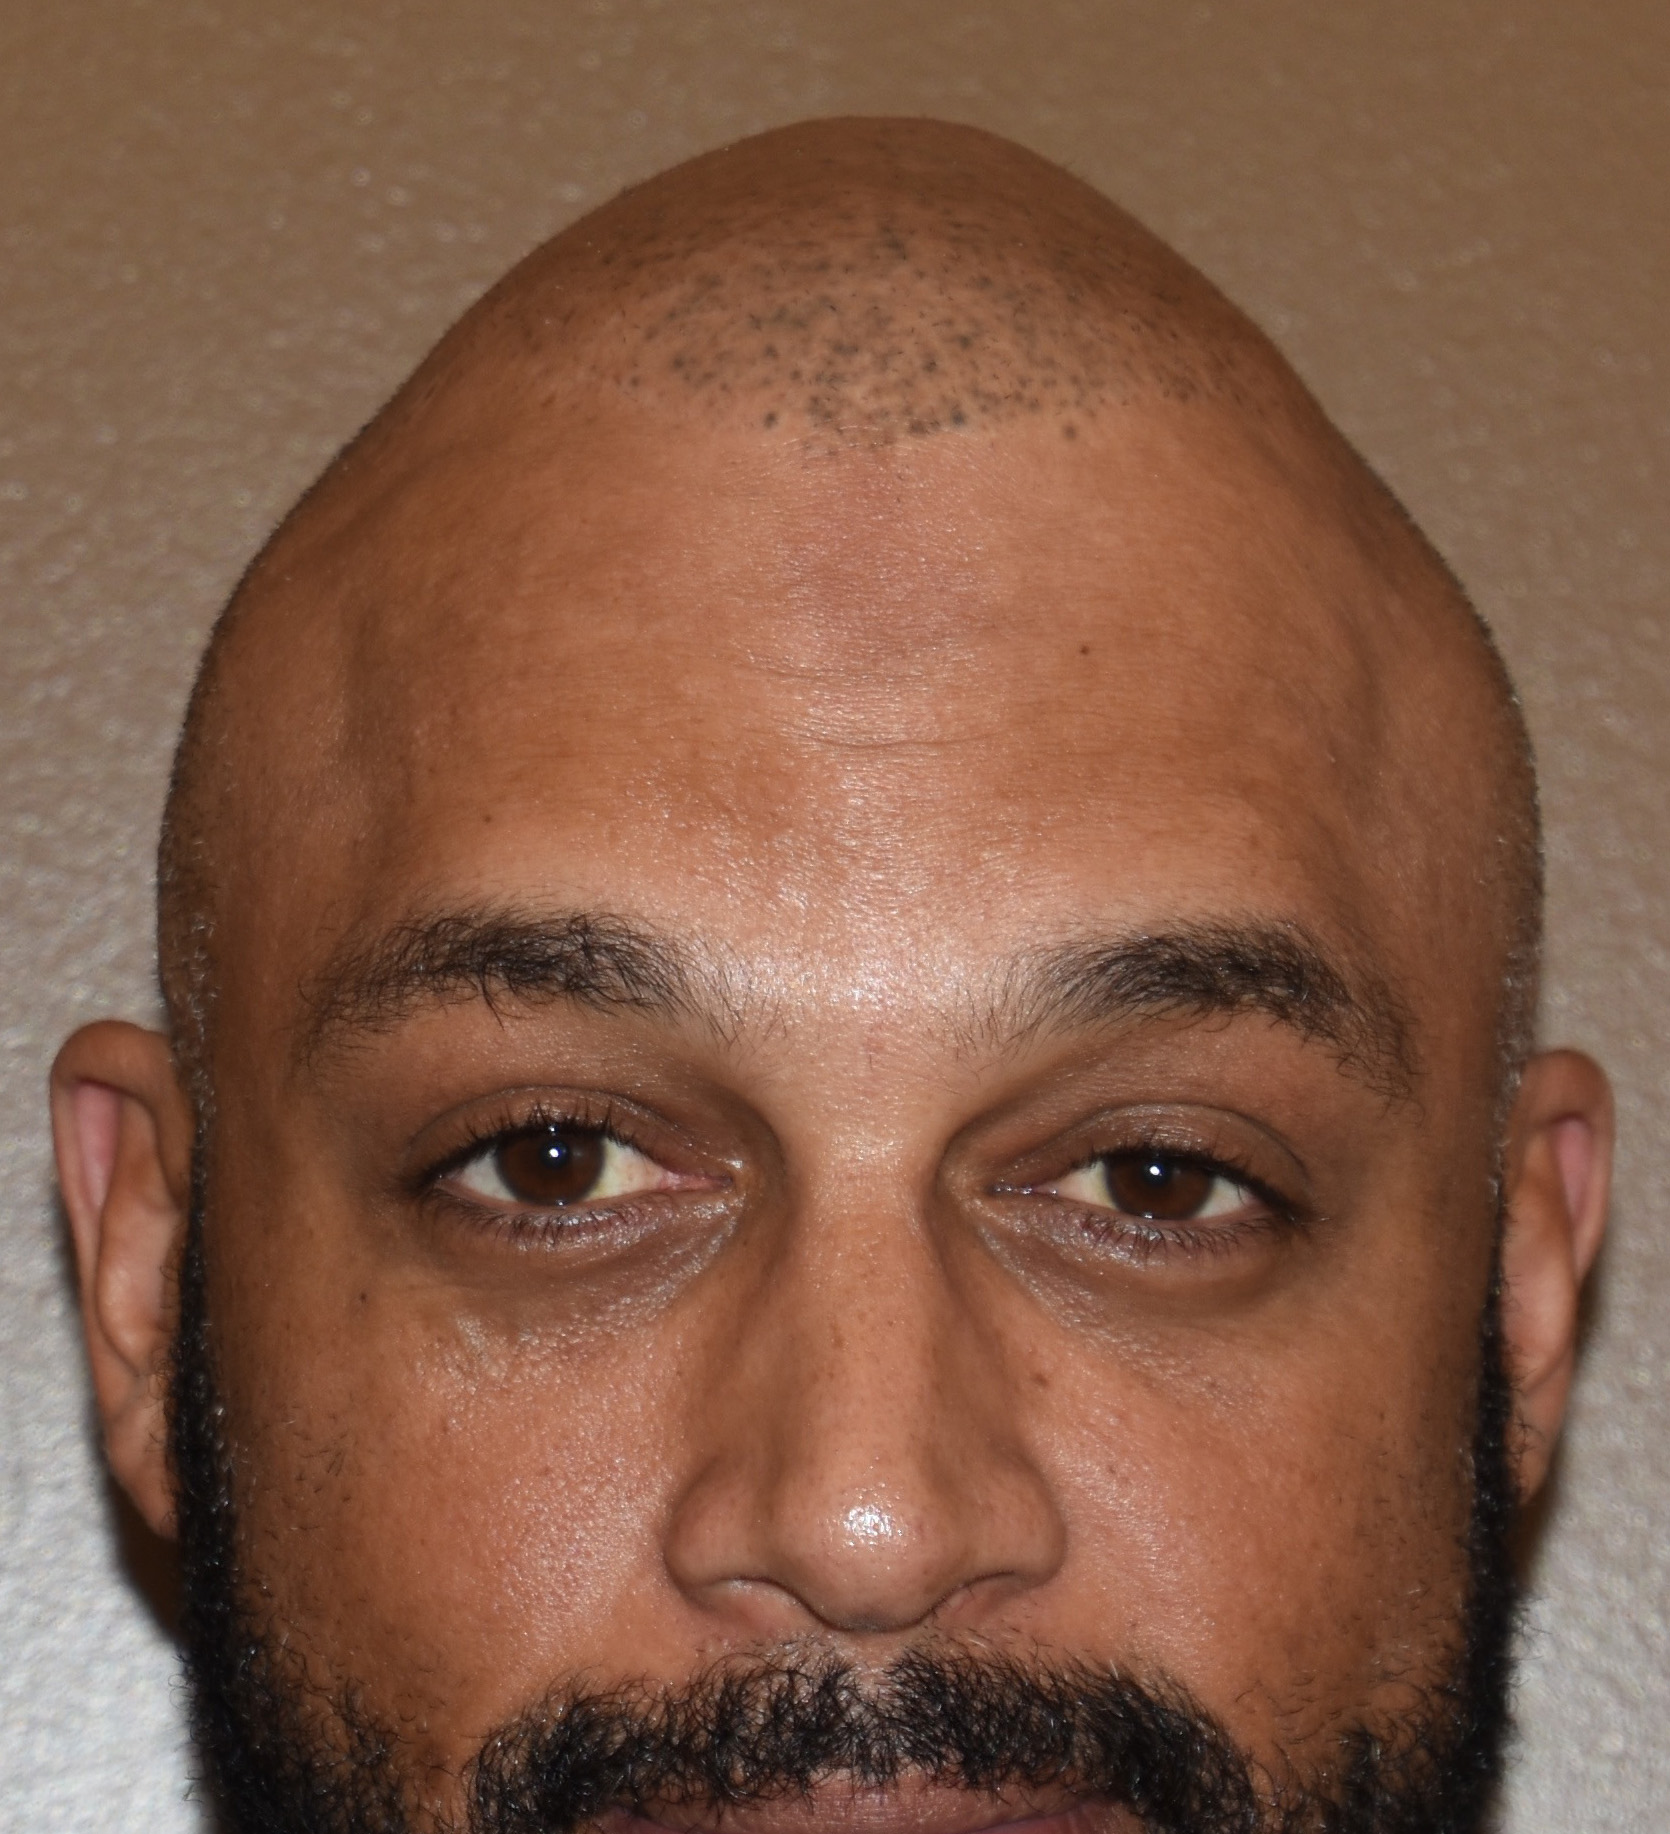

Patient 100

Desire for reshaping of an asymmetric flat back of the head in a shaved head male.

A combined back of the head reshaping procedure was done with a custom skull implant, sagittal ridge reduction and a right temporal muscle reduction.

Desire for reshaping of an asymmetric flat back of the head in a shaved head male.

A combined back of the head reshaping procedure was done with a custom skull implant, sagittal ridge reduction and a right temporal muscle reduction.